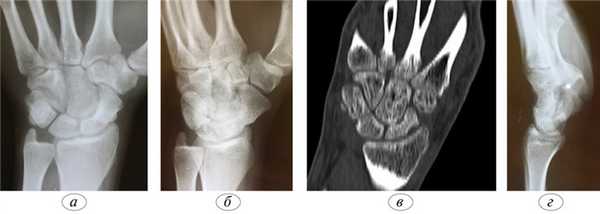

Функция пальцев полная. Сила кулачного схвата правой (доминантной) кисти — 22 кг, снижена почти в 2 раза по сравнению с нормой. Сила схвата левой кисти — 40 кг. Оценка по шкале ВАШ — 3 балла, по опроснику DASH — 21,16 балла. На рентгенограмме (рис. 5, а, б, в) и при компьютерной томографии выявлен ложный сустав ладьевидной кости (см. рис. 6, г). Рис. 6. Пациент К., 19 лет. Диагноз: ложный сустав ладьевидной кости правой кисти. а — рентгенограмма в прямой проекции; б — рентгенограмма в ¾; в — рентгенограмма в боковой проекции; г — компьютерная томография.

Через 8 нед после операции, по данным лучевой диагностики/рентгенограммы и компьютерной томографии (рис. 7, а, Рис. 7. Пациент К., 19 лет. Диагноз: ложный сустав ладьевидной кости правой кисти. Через 8 нед после операции. а — рентгенограмма в прямой проекции; б — рентгенограмма в ¾; в — рентгенограмма в боковой проекции; г — компьютерная томография, сагиттальная проекция; д — компьютерная томография, аксиальная проекция. б, в), сращение было достигнуто. Спицы удалили.